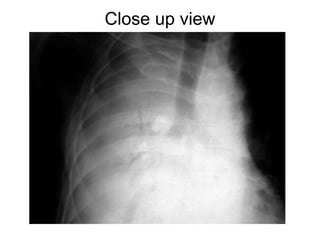

Close up view

Open bronchus sign

Open Bronchus Sign/ Alveolar Atelectasis • Presence of air bronchogram in atelectatic lung. • indicates that the airways are patent. • Commonly seen in adhesive alveolar atelectasis.